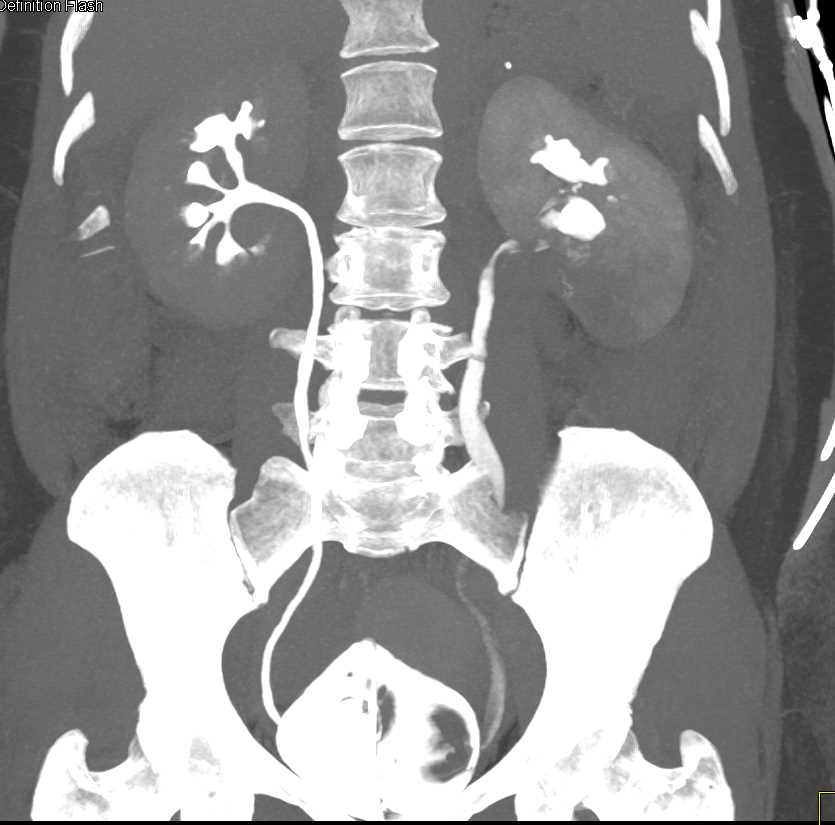

Acute Pyelonephritis Right Kidney